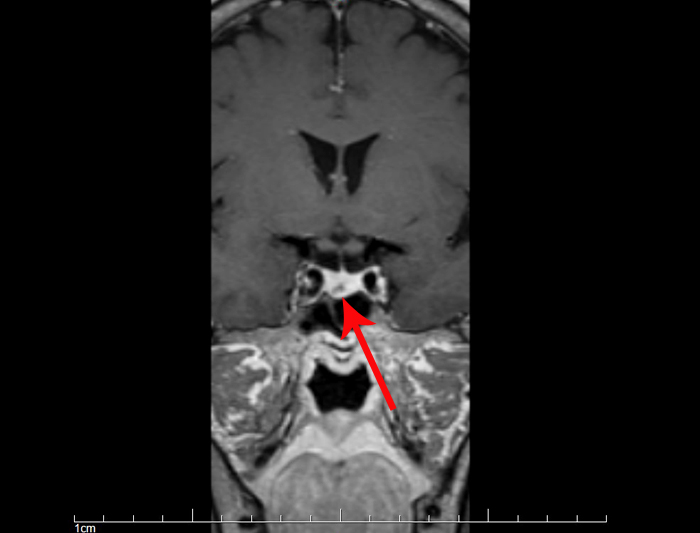

医生发现王先生鼻翼宽、齿缝大、下颌突出、皮肤褶皱深、手指脚趾像戴了“膨胀手套”——这正是垂体瘤的典型体征!垂体激素检查显示生长激素爆表,核磁检查显示垂体微腺瘤:原来王先生体重难控、代谢崩盘的罪魁祸首藏在大脑里!“我还以为胖就是吃多了动少了,原来激素在背后搞破坏!”王先生恍然大悟:“要不是医生‘会相面’,我还在盲目减肥浪费时间和精力!” 现在,王先生不仅自己坚持对症治疗,还拽着胖儿子来筛查——肥胖的可能病因!